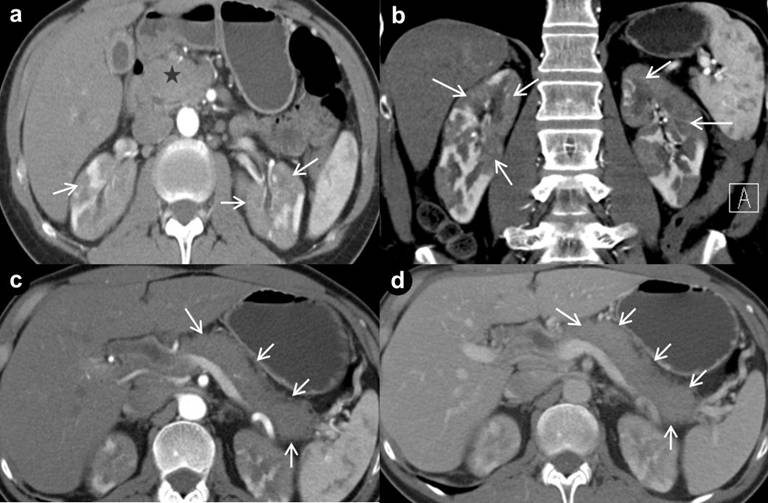

Computed tomography (CT) scan of the abdomen demonstrated an enlarged, sausage-shaped pancreas with mildly decreased enhancement on arterial phase and common bile duct dilation with tapering of the distal duct indicative of a benign stricture. Hypoenhancing non-cystic mass lesions were noted in bilateral renal parenchyma in all three phases (Figure 1). An endoscopic ultrasound revealed a diffusely hypoechoic pancreas without a mass lesion and an upper endoscopy was performed to obtain biopsies of the major papilla for IgG4 staining. The major papilla was prominent but biopsies demonstrated normal duodenal mucosa with only rare IgG4 staining cells present.

Figure 1. Pre treatment axial (a.) and coronal (b.) CT demonstrates enlarged pancreas and patchy areas of decreased enhancement in bilateral renal parenchyma (arrows). Diffusely enlarged pancreas (arrows) demonstrating the body and tail in arterial phase (c.) and in venous phase (d.). |